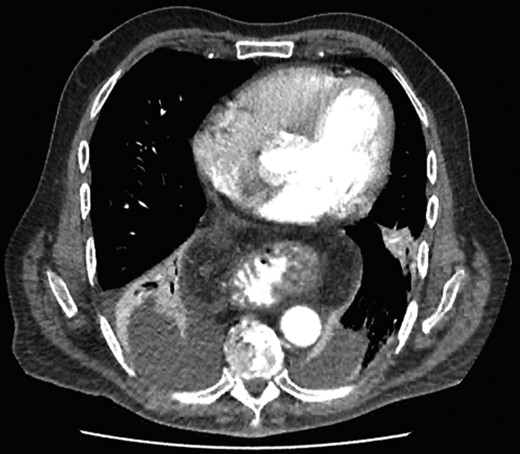

Computer tomography pulmonary angiogram (CTPA) done given recent surgery reported distal esophagus perforation with bibasal pleural effusion. No pulmonary embolism (Fig. 1).

Hiatus hernia with associated mural thickening of esophagus and locules of gas showing localized perforation.